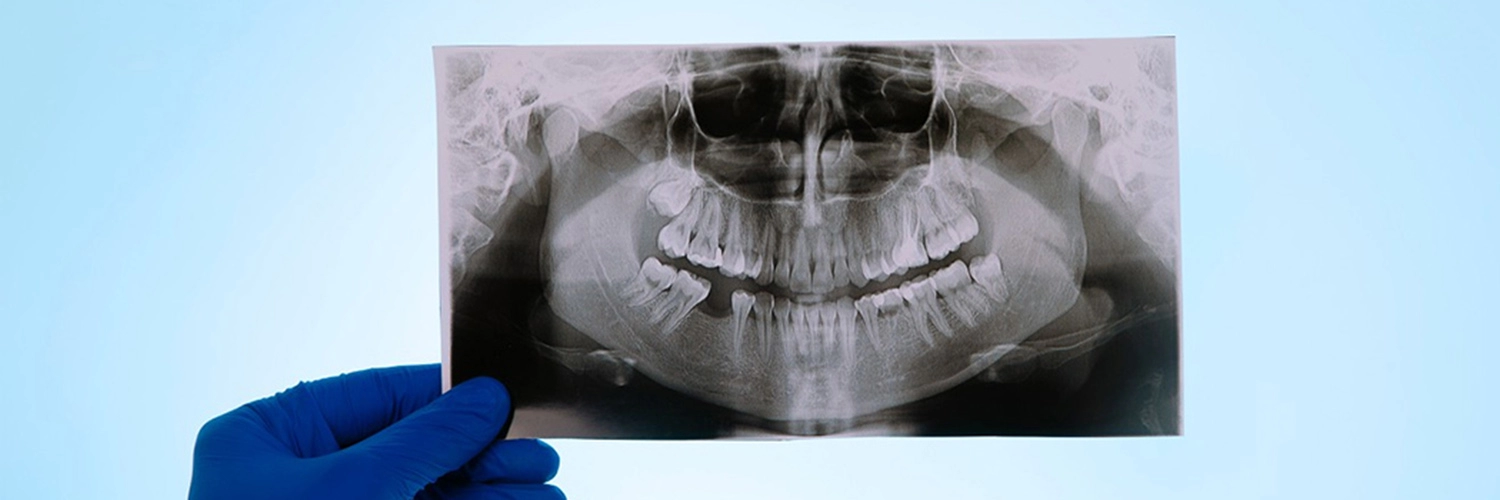

Этап диагностики является обязательным для всех пациентов для составления точной клинической картины. Это полностью бесплатно. Пациента осматривает хирург совместно с ортопедом, составляют фотопротокол и делают КТ. В консультационном кабинете на большом мониторе пациенту показывают все снимки и рассказывают о текущей клинической картине и возможном лечении. План лечения составляется в конце, согласовывается с пациентом. После подписания цена на лечение не меняется.